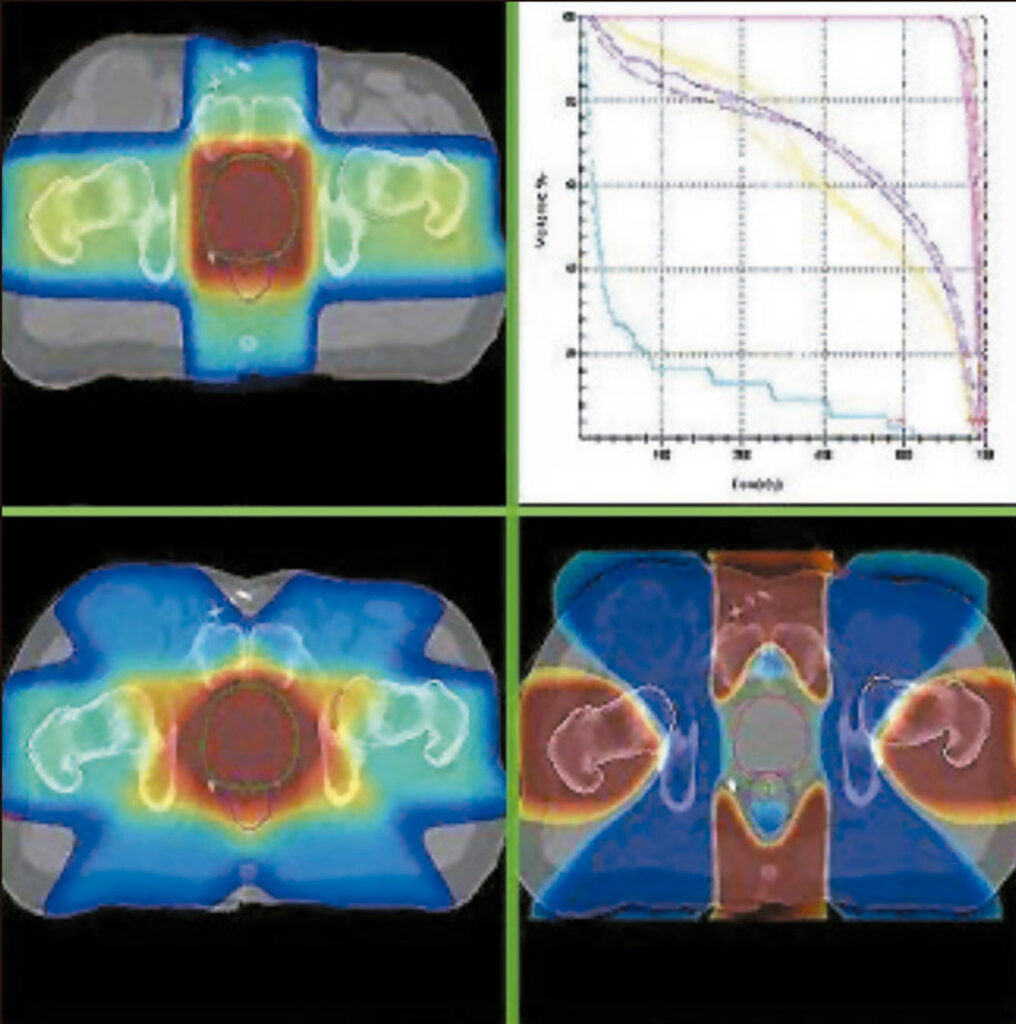

Los médicos radioterapeutas delinean los volúmenes de interés, tumor y órganos sanos, definen las funciones objetivos, es decir, establecen las relaciones Dosis-Volumen que desean obtener y adoptan una estrategia de fraccionamiento apropiada. Luego se diseña una configuración de múltiples haces.

IMRT emplea por primera vez en Radioterapia el concepto “Planificación Inversa”, en la cual, a diferencia de métodos anteriores, los médicos prescriben en la etapa inicial cuáles son los resultados deseados en términos de relaciones Dosis-Volumen y la estación de trabajo IMRT converge a la solución propuesta, obteniéndose mapas de campos de intensidades variables mediante un complejo proceso de iteración.

La Planificación Inversa ofrece el escenario óptimo para tratar a cada paciente en particular, liberando altas dosis en el tumor y minimizando la dosis en los tejidos sanos.

Optimización de la Isodosis Terapéutica en tumor, preservando la médula.